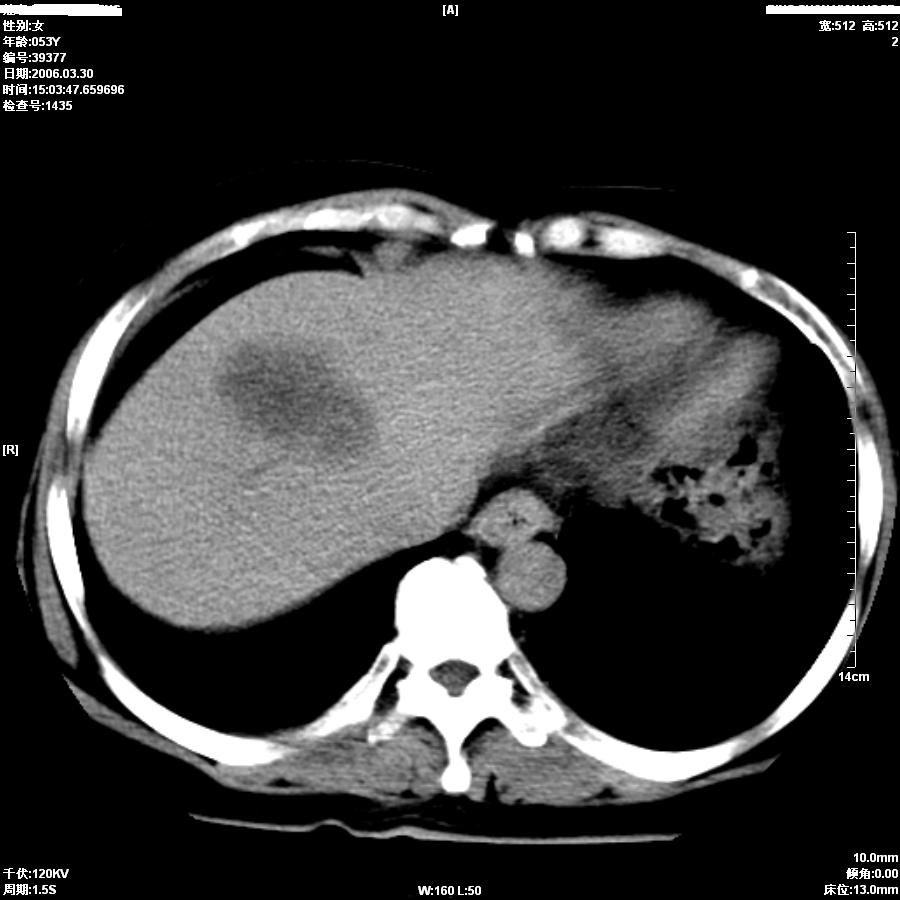

女,50岁,上腹部憋胀,疼痛月余。做增强刚打了50ml造影剂病人就出现了较重的过敏,所以强化不成功。

支持肝癌伴左叶外侧段肝内胆管轻度扩张。

平扫第8图胆总管内似见结石,上部胆道扩张,肝内片影无强化,胆囊不清,胃小弯壁略厚。

考虑1胆结石伴低微弹道梗阻及肝内感染2胆管癌。

因为没有完整的强化,该病例我首先考虑是肝内胆管细胞癌.患者因为有过敏我建议行mri.

从平扫:肝脏肿块,胰头周围结构不清似有结节。考虑恶性肿瘤(首先要排外肝胆感染病变)。胆管癌>肝癌。建议mri。

较典型胆管癌。

胆管细胞癌可能性大

胆总管扩张,未见明显结石征象。还是胆管细胞ca可能大

提示肝内胆管细胞癌。

肝内胆管癌 累及肝门

如果胆囊未切除,首先考虑胆囊癌肝侵犯。

中老年妇女,肝门、胆囊区病变,病变实体形态欠清楚,胆囊癌可能性极大。

鉴别诊断:肝癌;胆管癌;

理由:1、低密度病灶,动脉期末有一点强化。

2、左肝内胆管扩张。

3、肝门区胆管壁静脉期有强化。